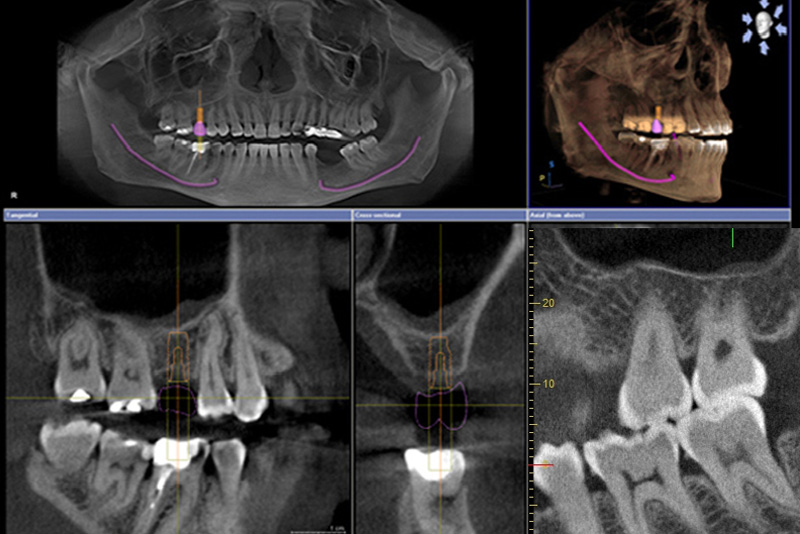

歯科用CT(コンピュータ断層撮影)は、一般的なレントゲンと異なり3次元画像で歯根の形状や神経の位置を正確に把握できる。一般的には保険が適用(2011年~)では3,000円前後、自由診療の場合は5,000円〜15,000円。

歯科医用CT(上画像)はすごいものだ

医師がきて神経の痛みを検査した後で、CT画像を動かしながら説明してくれた。

レントゲン撮影では影しか映らない。

しかし、CTでは3D撮影。だから画像をグリグリ回転でき、いろんな角度から観察できる。

これにはスゴク驚いた。

「歯根の片方が溶けちゃってますが、残ってる歯根を生かして治療を続けましょうか。」

拡大して説明してくれたCT画像をみると、たしかに片方の歯の根元がすごく短かった。

「フ~ム奥歯が、こんなになっちゃてたのか。」って理解した。